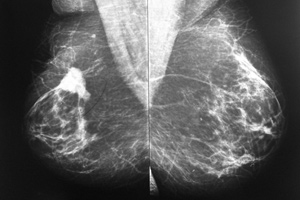

Uso de Inteligencia Artificial para detectar enfermedades

El caso del cáncer de mama

Imagen: SCiardullo